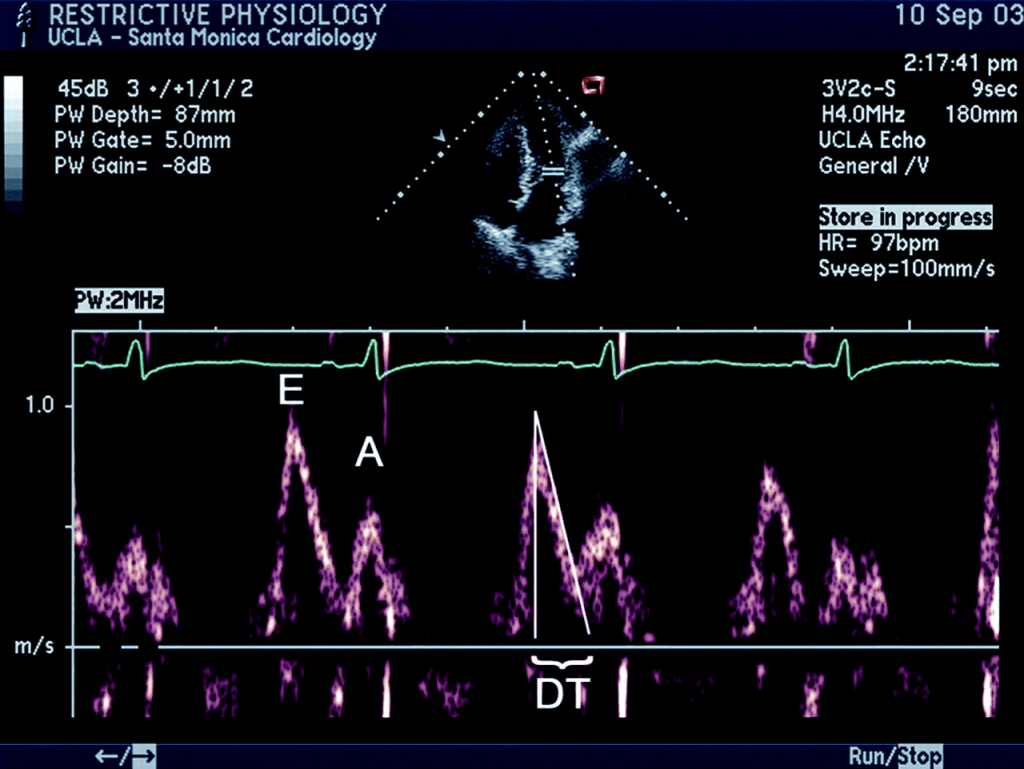

Restrictive LV filling is an advanced form of diastolic dysfunction. The mean LA pressure is high, and LVEDP is also correspondingly elevated (need not be linear though, as LA reservoir/conduit dysfunction can independently hike the LA pressure). This clinical scenario of restrictive LV filling usually occurs as part of HFpEF, though it can occur in HFrEF as well. (25% of DCM have restrictive filling)

Some physicians use the E-DT as a visual guide (Deceleration time of E velocity, which is inversely related to the degree of restriction). Normal is more than 150 ms. In most restrictive filling, it is 100 ms or less. Diuretic dose can be adjusted based on E-DT.

I have tried a personal working formula for optimal diuretic dose. It can be titrated upwards ,twice the value of E-DT when it is less than 100 ms.(Eg if E-DT is 80ms Frusemide can be 160mg, but, note there is an U curve in this .If DT is too short, diuretics will worsen the hemodynamics .At 60 ms E-DT diuretics need to be reduced to 120 mg )